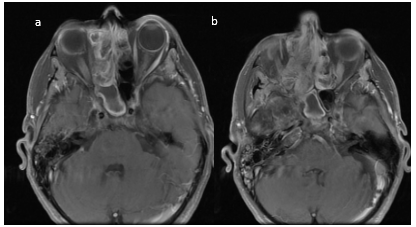

En RM con contraste la lesión presenta un realce intenso al gadolinio (Figura 11 – 12 – 13).